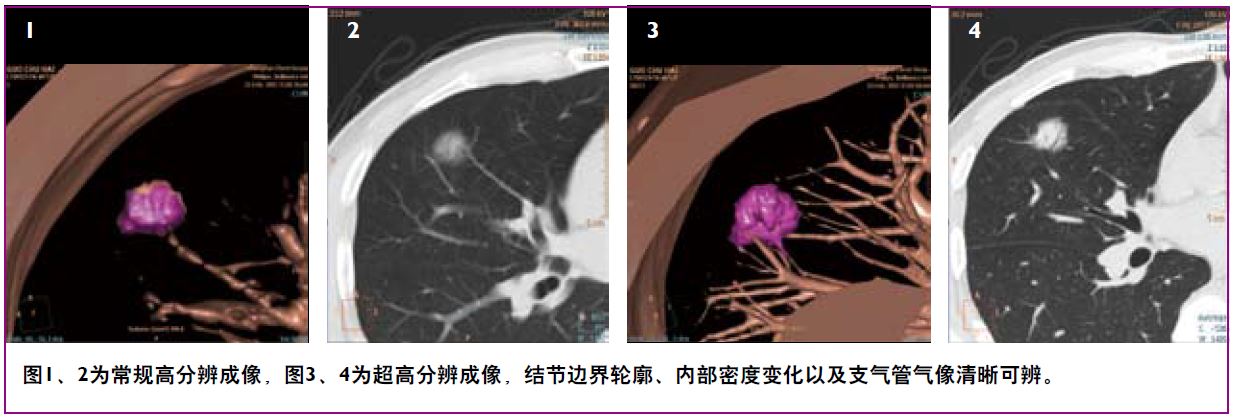

显微成像——动态四焦点及纳米探测器实现4800采样/0.27秒最高采样率,丰富信息成就1024x1024超高分辨成像技术,4倍信息量提升令微小病灶诊断不再困惑。同时高效的祛金属伪影O-Mar功能防止漏诊情况。

1024x1024高清成像对于肺结节显示加倍的清晰